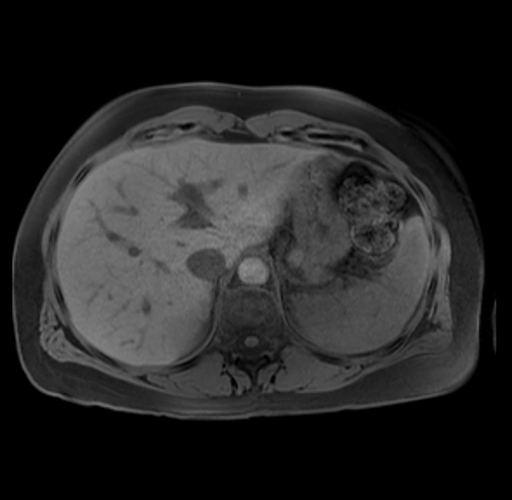

Imaging Analysis

Look through the patient's CT scan to identify any areas of concern for the necessary procedure.

Based on your CT findings, which issue(s) are present and would give reason for "planned slowing down moment(s)" in this case?

Considering a standard distal pancreatectomy procedure, what step(s) of the operation would you do differently in this case?